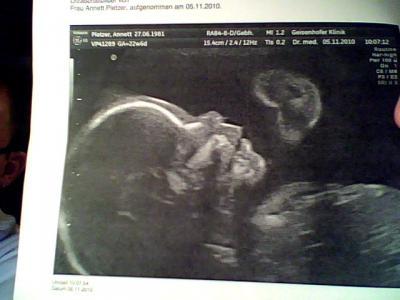

nach den Wochen des Wartens waren wir gestern nun endlich in München, und er hat keine Spalte, das hat mich echt fertig gemacht , es war eine fixe Idee dass er das auch hat und ja es war einfach schlimm. er wiegt nun 560gr und ist 29cm groß

Bild zu Gestern Pränataldiagnostik - Forum für März - Mamis

Schön, dass es Deinem Zwergl so gut geht und er schön gewachsen ist.... Sehr schöne Bildchen hast Du da. glg